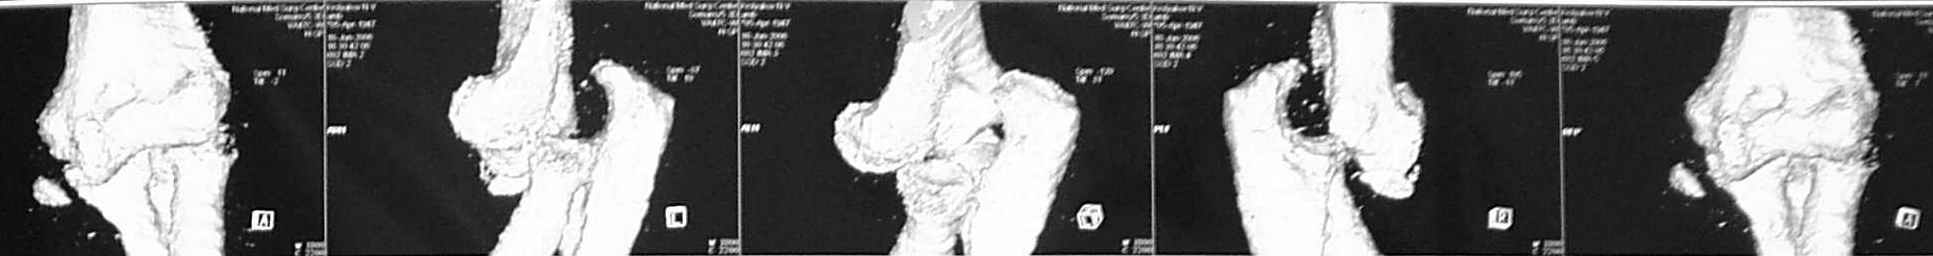

3 недели лечился в травмпункте с диагнозом отрывной перелом медиального надмыщелка левой плечевой кости (Rtg-1). Лечение состояло в ношении руки на косыночной повязке. Затем в другом учреждении сделали КТ (рис 2,3,4).

Неврологии нет, выраженный отек, активные движения в объеме 60 градусов. Сейчас прошло 4 недели после травмы.

Что же все-таки сломано? Что бы Вы сделали (или не стали бы делать)?